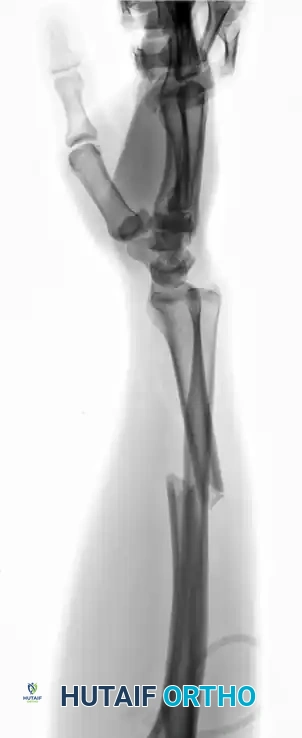

Galeazzi Fracture-Dislocations

A Galeazzi injury involves a fracture of the distal third of the radial shaft coupled with a dislocation or subluxation of the DRUJ. These are highly unstable injuries that mandate operative intervention in adults.

The radius must be anatomically reduced and rigidly fixed, typically utilizing a dynamic compression plate (DCP) or a locking compression plate (LCP). Following radial fixation, the DRUJ must be assessed for stability throughout the forearm arc of motion. If the DRUJ remains unstable, it is often pinned in supination using parallel Kirschner wires.